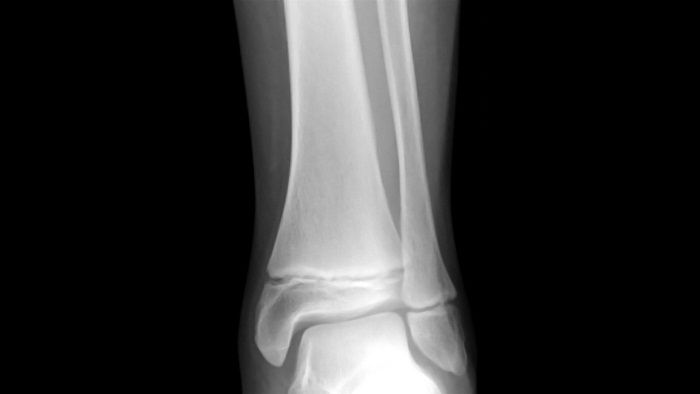

- Chụp X quang tuổi xương và phải được đọc bởi bác sỹ chuyên khoa có kinh nghiệm. chụp hệ thống xương ở những trẻ có nghi ngờ loạn sản xương như những trường hợp có bất thường tỷ lệ các phần của cơ thể, hoặc những trẻ có SDS chiều cao dưới chiều cao trung bình của bố mẹ và phải được các bác sỹ chuyên khoa chẩn đoán hình ảnh đọc.

- Tuổi xương chậm, mức độ chậm liên quan đến cả mức độ nặng và thời gian thiếu GH

Gãy sụn tăng trưởng hay gãy mảng tăng trưởng là tình trạng tổn thương ở phần sụn nằm gần các đầu xương của trẻ. Sụn tăng trưởng có ở các xương dài của cơ thể, ví dụ như xương đùi, xương quay và xương trụ của cẳng tay. Sụn tăng trưởng là phần xương cứng lại sau cùng và là phần mềm nhất, yếu nhất của cấu trúc xương, thậm chí đôi khi còn yếu hơn các dây chằng và gân xung quanh. Do xương của trẻ em yếu hơn xương người lớn nên những chấn thương vốn chỉ gây bong gân ở người lớn có thể gây gãy sụn tăng trưởng ở trẻ.